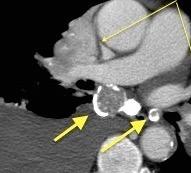

Síntomas y signos que se producen con la obstrucción total o parcial de la vena cava superior

Causas Malignas +/- 90-95%

Ca. Broncogénico (80-85%)

Linfoma No Hodgkin (15%)

Catéteres, shunts y marcapasos…23%

T. Mediastínico. Bocio

Fibrosis Idiopática

Tb, Histoplasmosis, Actinomicosis, Sarcoidosis

Carcinoma microcítico con síndrome de VCS

Grupos:

1. Obstrucción por encima de la V Ácigos. (La sangre llega al corazón a través de ella)

2. Obstrucción con participación de la V. Ácigos. (La sangre utiliza otras alternativas para llegar al corazón vía VCI).

Participación de la V. Ácigos como vía principal para llegar a la VCI.

Visible: 88%